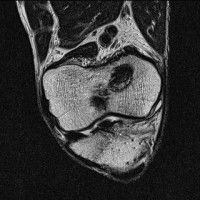

무릎 mri 간단히 봐주실 수 있으시나요 ㅠㅠ

안녕하세요 8년전 십자인대 수술하고 최근 무리한 운동에 무릎 불편감이 생겨서

mri 찍었습니다.

진단결과는 첫 찍은 병원에서 활액막염 이라는 진단을 받았습니다. 혹시 봐주실 수 있으실까요?

올라온 MRI가 단편적이라서 정확한 진단에 어려움이 있지만 십자인대에는 큰 이상이 있지는 않은것 같으며, 무릎관절내 물이 있는 것으로 보아 활액막염의 진단이 맞을 것 같습니다.

하지만 단편적인 영상이기 때문에 촬영병원에서 정확한 판독지 등을 받으시는 것이 좋겠습니다.